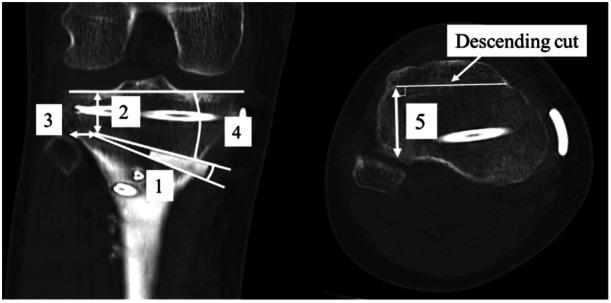

No cases were found with a hinge position above PTFJ, 41 cases were within PTFJ, and one case was distal to PTFJ. Hinge fractures were observed in 10 patients (23.8%). According to the hinge position classification, seven cases were type I (a fracture within PTFJ), three were type II (a fracture that reaches the distal portion of PTFJ), and no cases were type III (intra-articular fracture). The anteroposterior hinge width measured perpendicular to the descending cut of the flange on axial CT images at the proximal level of the PTFJ was significantly shorter in the hinge fracture group ( = 0.03).

本研究检查了42例行owDTO的膝关节。通过术后计算机断层扫描(CT)图像测量铰链区域周围的距离和角度,研究胫腓近端关节(PTFJ)铰链骨折的水平。根据既往报道对铰链位置进行分类,并评估铰链骨折情况。

未发现铰链位置高于PTFJ的病例,41例在PTFJ内,1例在PTFJ远端。10例患者(23.8%)观察到铰链骨折。根据铰链位置分类,7例为I型(PTFJ内骨折),3例为II型(骨折延伸至PTFJ远端部分),无III型(关节内骨折)病例。在PTFJ近端水平的轴向CT图像上,垂直于凸缘下行切口测量的前后铰链宽度在铰链骨折组明显更短(=0.03)。